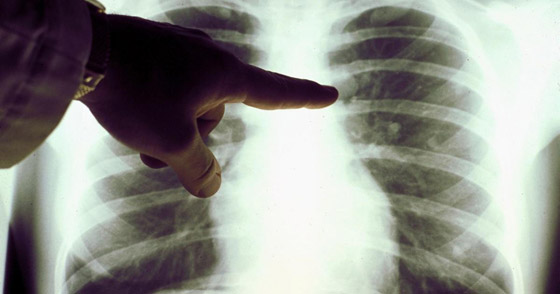

حذر أطباء متخصصون من أن تورم الوجه قد يكون علامة رئيسية على الإصابة بسرطان الرئة. يحدث تورم الوجه عندما يضغط الورم على الوريد الأجوف العلوي (SVC)، الذي يربط الرأس بالقلب، إذ يشير الأطباء إلى أن أغلب حالات انسداد الوريد الأجوف العلوي (SVCO) ناتجة عن سرطان الرئة.

ولفت الأطباء إلى أن معظم حالات انسداد الوريد الأجوف العلوي ناتجة عن سرطان الرئة أو انتشار المرض إلى الغدد الليمفاوية القريبة، بحيث تصبح منتفخة.

أعراض مالوفة

كما كشف الخبراء بالمجال أنه بالإضافة إلى تورم الوجه، قد يحصل تورم في الرقبة والذراعين وأعلى الصدر بسبب ضغط الوريد. كما تشمل الأعراض المصاحبة الأخرى ضيق التنفس أو الصداع أو تغيرات في البصر، أو ظهور أوردة زرقاء على الصدر أو الدوخة. وسرطان الرئة نادر الحدوث لدى من تقل أعمارهم عن 40 عاما، ويؤثر في الغالب على كبار السن.

ودعا أطباء إلى الإقلاع عن التدخين فورا كونه السبب الرئيسي، حيث تشير إحصائيات علمية إلى أن المدخنين يتصدرون الإصابة بهذا المرض بنسبة 70% من الإصابات.